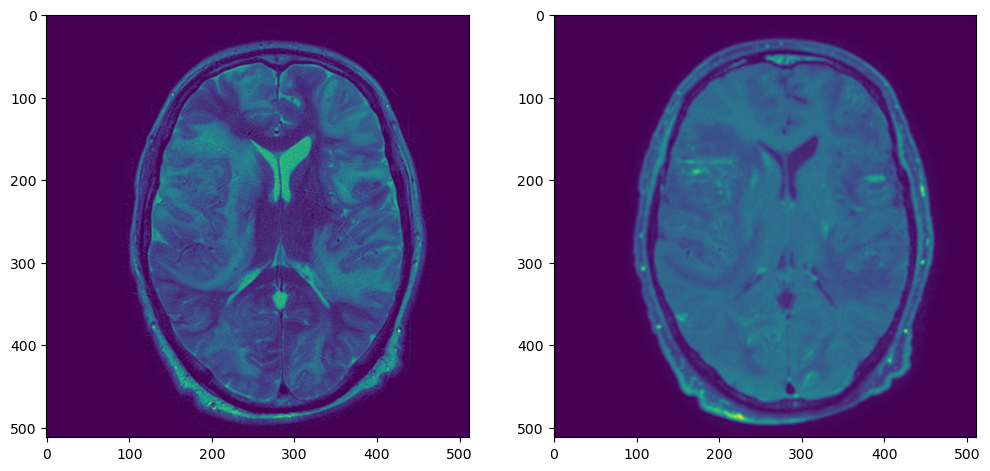

plt.figure(figsize=(12,6))

plt.subplot(121)

plt.imshow(t2_sitk_array[t2_sitk_array.shape[0]//2,:,:])

plt.subplot(122)

plt.imshow(t1_resampled_array[t1_resampled_array.shape[0]//2,:,:])

t2t1resampled

Работает гораздо быстрее: